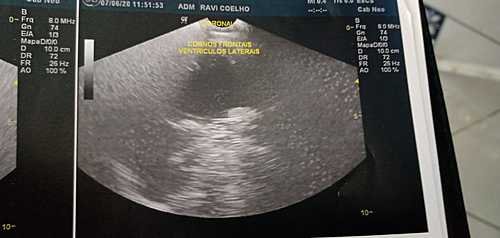

Sou a Rafaelli mãe do Ravi! Vou contar a história do meu filho. Ravi atualmente está com 6 meses, nasceu lindo e saudável, passando os dias, percebemos que nas suas fezes começou a sair sangue, entre idas e vindas de medicos, descobriramos que ele é APLV, e também é alérgico à outros alimentos (carne vermelha, ovos, trigo, algumas frutas e legumes), poucos meses depois, levei Ravi ao pediatra em uma consulta de rotina e descobriu que ele tem também Nistagmo na vista, então a médica o encaminhou para uma oftalmologista e um neurologista, saímos das consultas com mais exames , pois a neurologista pediu urgentemente 1 Ultrassonografia tansfontanela, pois com apenas 4 meses a moleira dele já havia se fechado e a testinha dele está formando um triângulo para a preocupação de todos. A médica suspeitou de craniostenose, uma deformidade no crânio muito sério que precisa de cirurgia para correção, antes que o bebê venha ter sequelas irreversíveis . Sendo assim com arrecadações de doações e também venda de rifa, conseguimos juntar o dinheiro do exame da fontanela, e foi constado que realmente ele tem a craniostenose, e também para nossa surpresa Hidrocefalia. Vamos fazer agora uma TC do crânio e TC das órbitas (oftalmologista pediu, pois há um esbranquiçado em uma delas) para irem mais a fundo do quadro e saber quando e como vão fazer essa cirurgia. Não temos condição de arcar com todos os custos, essas TC o plano não cobre por causa da carência, e pelo SUS sem data para realizar os exames, então terei que pagar, tenho também o gasto da minha alimentação, que é muito alto o custo, mais preciso ter uma alimentação saudável ,pois eu ainda amamento, além do leite especial que ele tem que tomar NEOCATE, que graças a Deus consegui pegar os papéis para dar entrada pelo governo e pegar sem custo dia 23 de outubro a consulta para pegar os leites, tem o dinheiro entre idas e vindas ao médico, agora também temos esses exames para realizar as TC do Crânio , e TC dá órbitas . Peço encarecidamente para vocês nos ajude com a quantia que for, vou ser grata eternamente. Desde já agradeço por toda atenção.